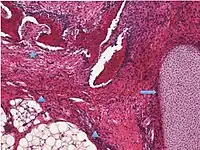

| Mucinous tumor | 15% | 8.8% | Benign mucinous tumors of the ovary consist of simple, nonstratified columnar epithelium with basally-located hyperchromatic nuclei and resemble gastric foveolar epithelium.[21] | ![]() |